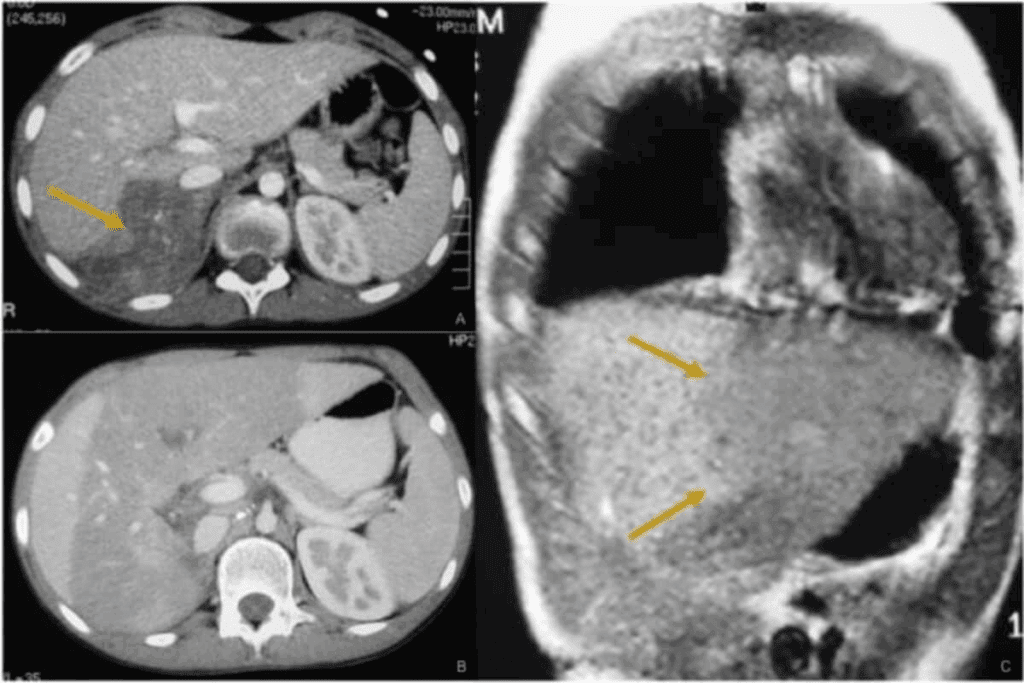

Imaging Techniques

Imaging is vital for finding and understanding neuroblastoma. We use:

- MRI (Magnetic Resonance Imaging): Shows detailed images of the tumor and nearby tissues.

- CT (Computed Tomography) scan: Checks the tumor’s size and how it affects nearby areas.

- MIBG (Metaiodobenzylguanidine) scan: Finds neuroblastoma cells, as many tumors take up MIBG.